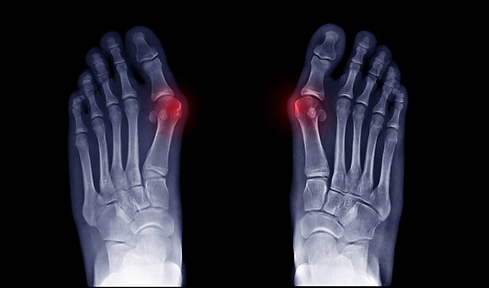

Hallux Valgus

Les manifestations cliniques de l’hallux valgus sont généralement aisément identifiables. Elles se traduisent par une déviation progressive du gros orteil vers l’extérieur, pouvant, dans les formes évoluées, entraîner un chevauchement du second orteil.

Cette déviation s’accompagne d’une désaxation de l’articulation métatarso-phalangienne du premier rayon, à l’origine de la formation d’une saillie osseuse caractéristique sur le bord interne de l’avant-pied, communément appelée « oignon ».